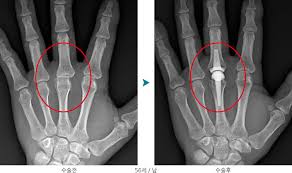

4.수술적 치료

치료가 효과적이지 않거나 심각한 경우, 수술적 치료가 필요할 수 있습니다. 관절 성형술은 관절 변형이 심각한 경우에 시행되며, 손상된 관절을 제거하고 인공 관절로 대체하는 수술입니다. 이렇게 수술을 통해 관절의 기능을 개선하고 통증을 감소시킬 수 있습니다.